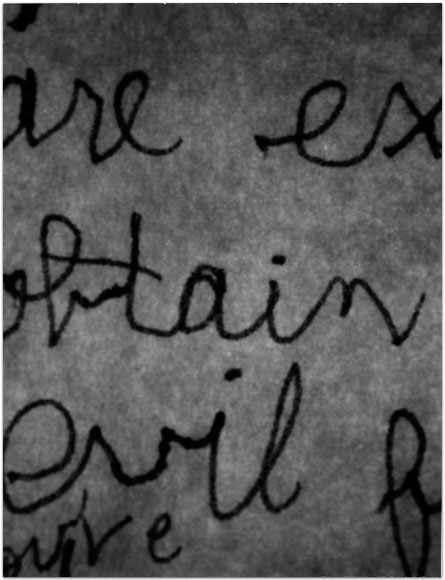

- Itis

- 2004

- 3.25″ × 4.25″

- Photographic montages of my hands & health paraphernalia on Polaroid Type 664 & 669 Film using a Daylab Printer.

- Frustrated by a lack of mobility and severe pain with my fingers, unable to accomplish any task requiring joint dexterity,

I noticed piles of health related papers strewn around. I layered these in a slide printer without removing

my hands, enlarging both onto the film.